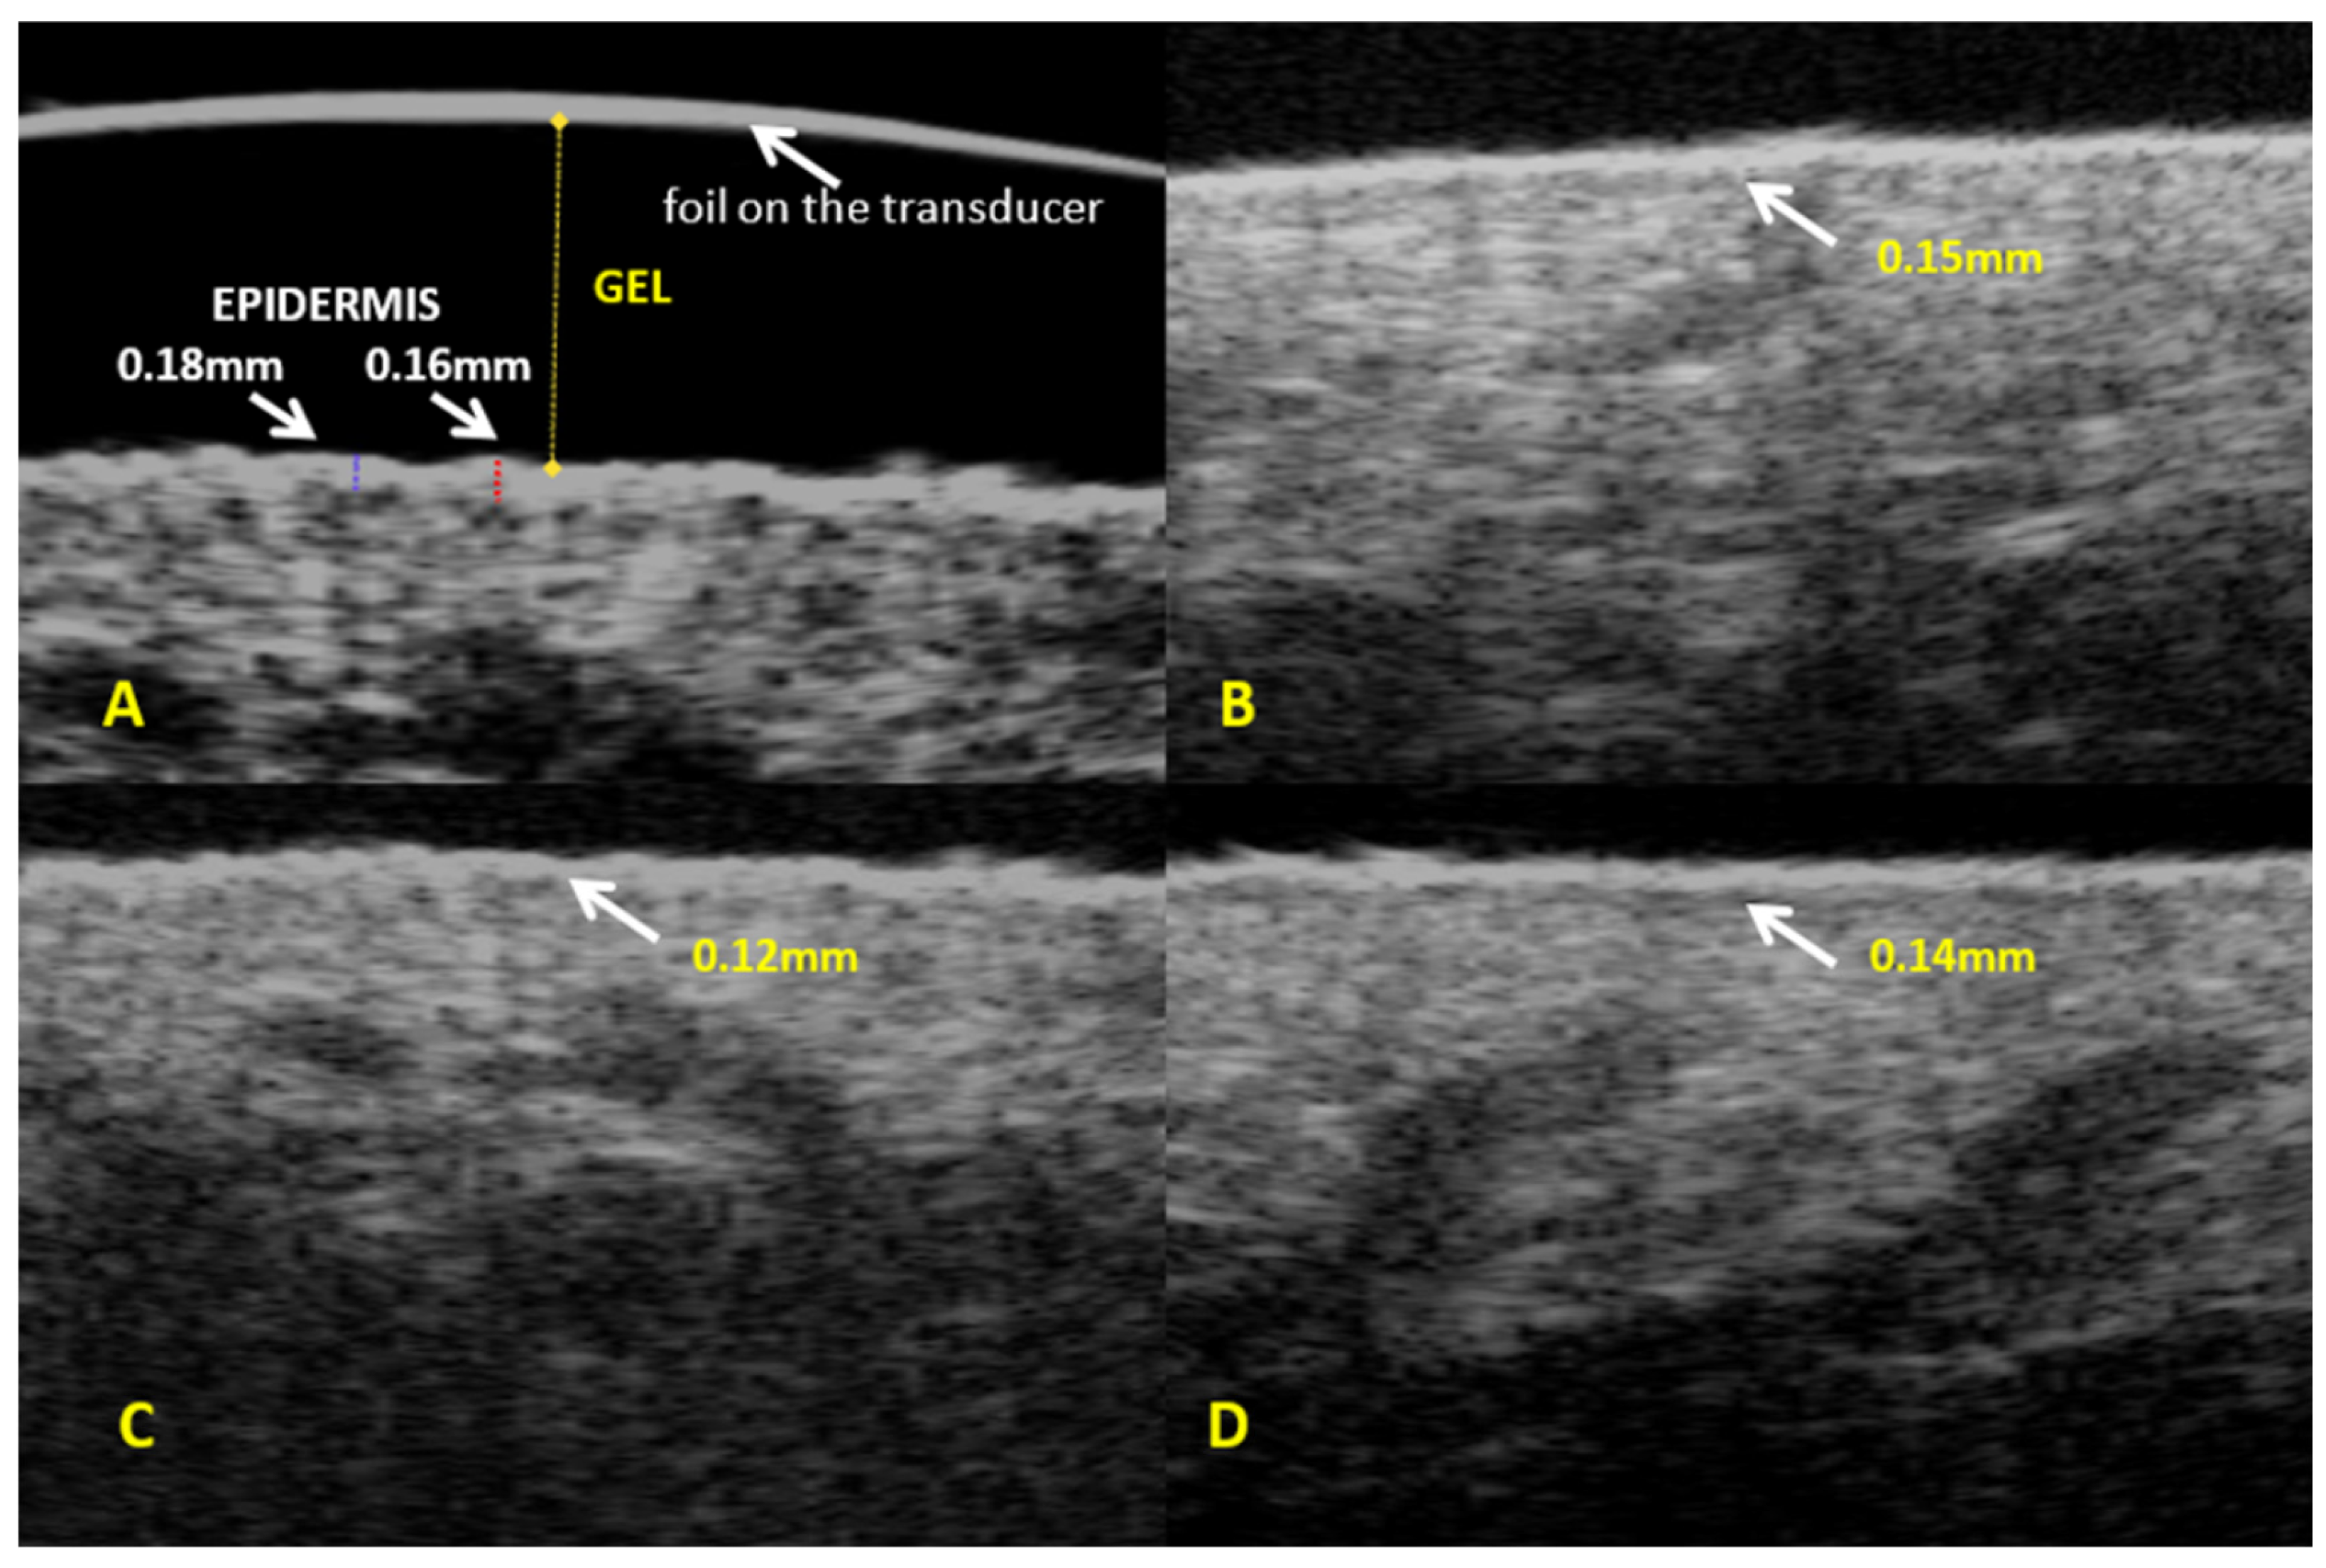

The mean epidermis thickness measured using high-frequency ultrasound in the entire study sample (n = 114) was 0.13 mm, SD = 0.03 mm (Table 1). Subgroup analysis demonstrated that the mean epidermis thickness was similar in three subgroups identified based on cellulite severity (0.12 mm, 0.13 mm, and 0.13 mm in groups 1, 2, and 3, respectively) with no significant between-group differences (Table 2, Figure 1 and Figure S1).

Figure 1. Ultrasound assessment of epidermis—(A). Epidermis thickness: (B)—group 1, (C)—group 2, (D)—group 3.